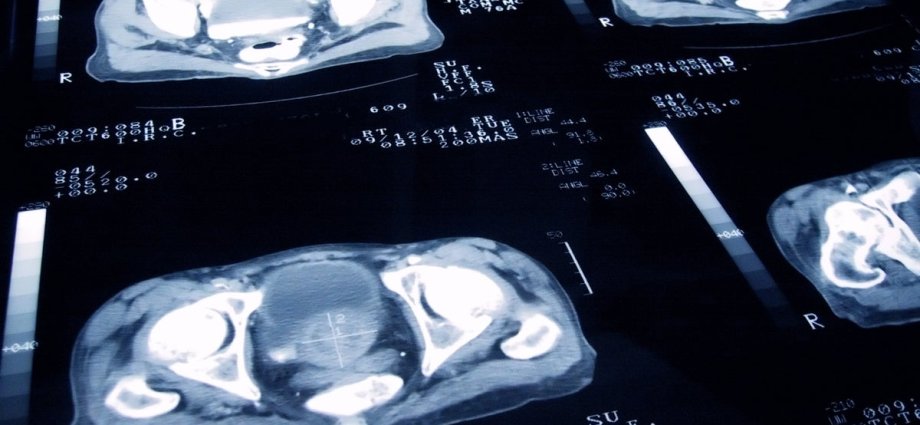

A major new prostate cancer screening trial, backed by £42 million of funding from Prostate Cancer UK and the Government, is looking at whether using MRI or other scans, combined with PSA, could tip the balance in favour of a nationwide screening programme.

The Transform trial, which is recruiting patients, is looking at whether a screening strategy would reduce deaths from prostate cancer while minimising harms from overdiagnosis and overtreatment.